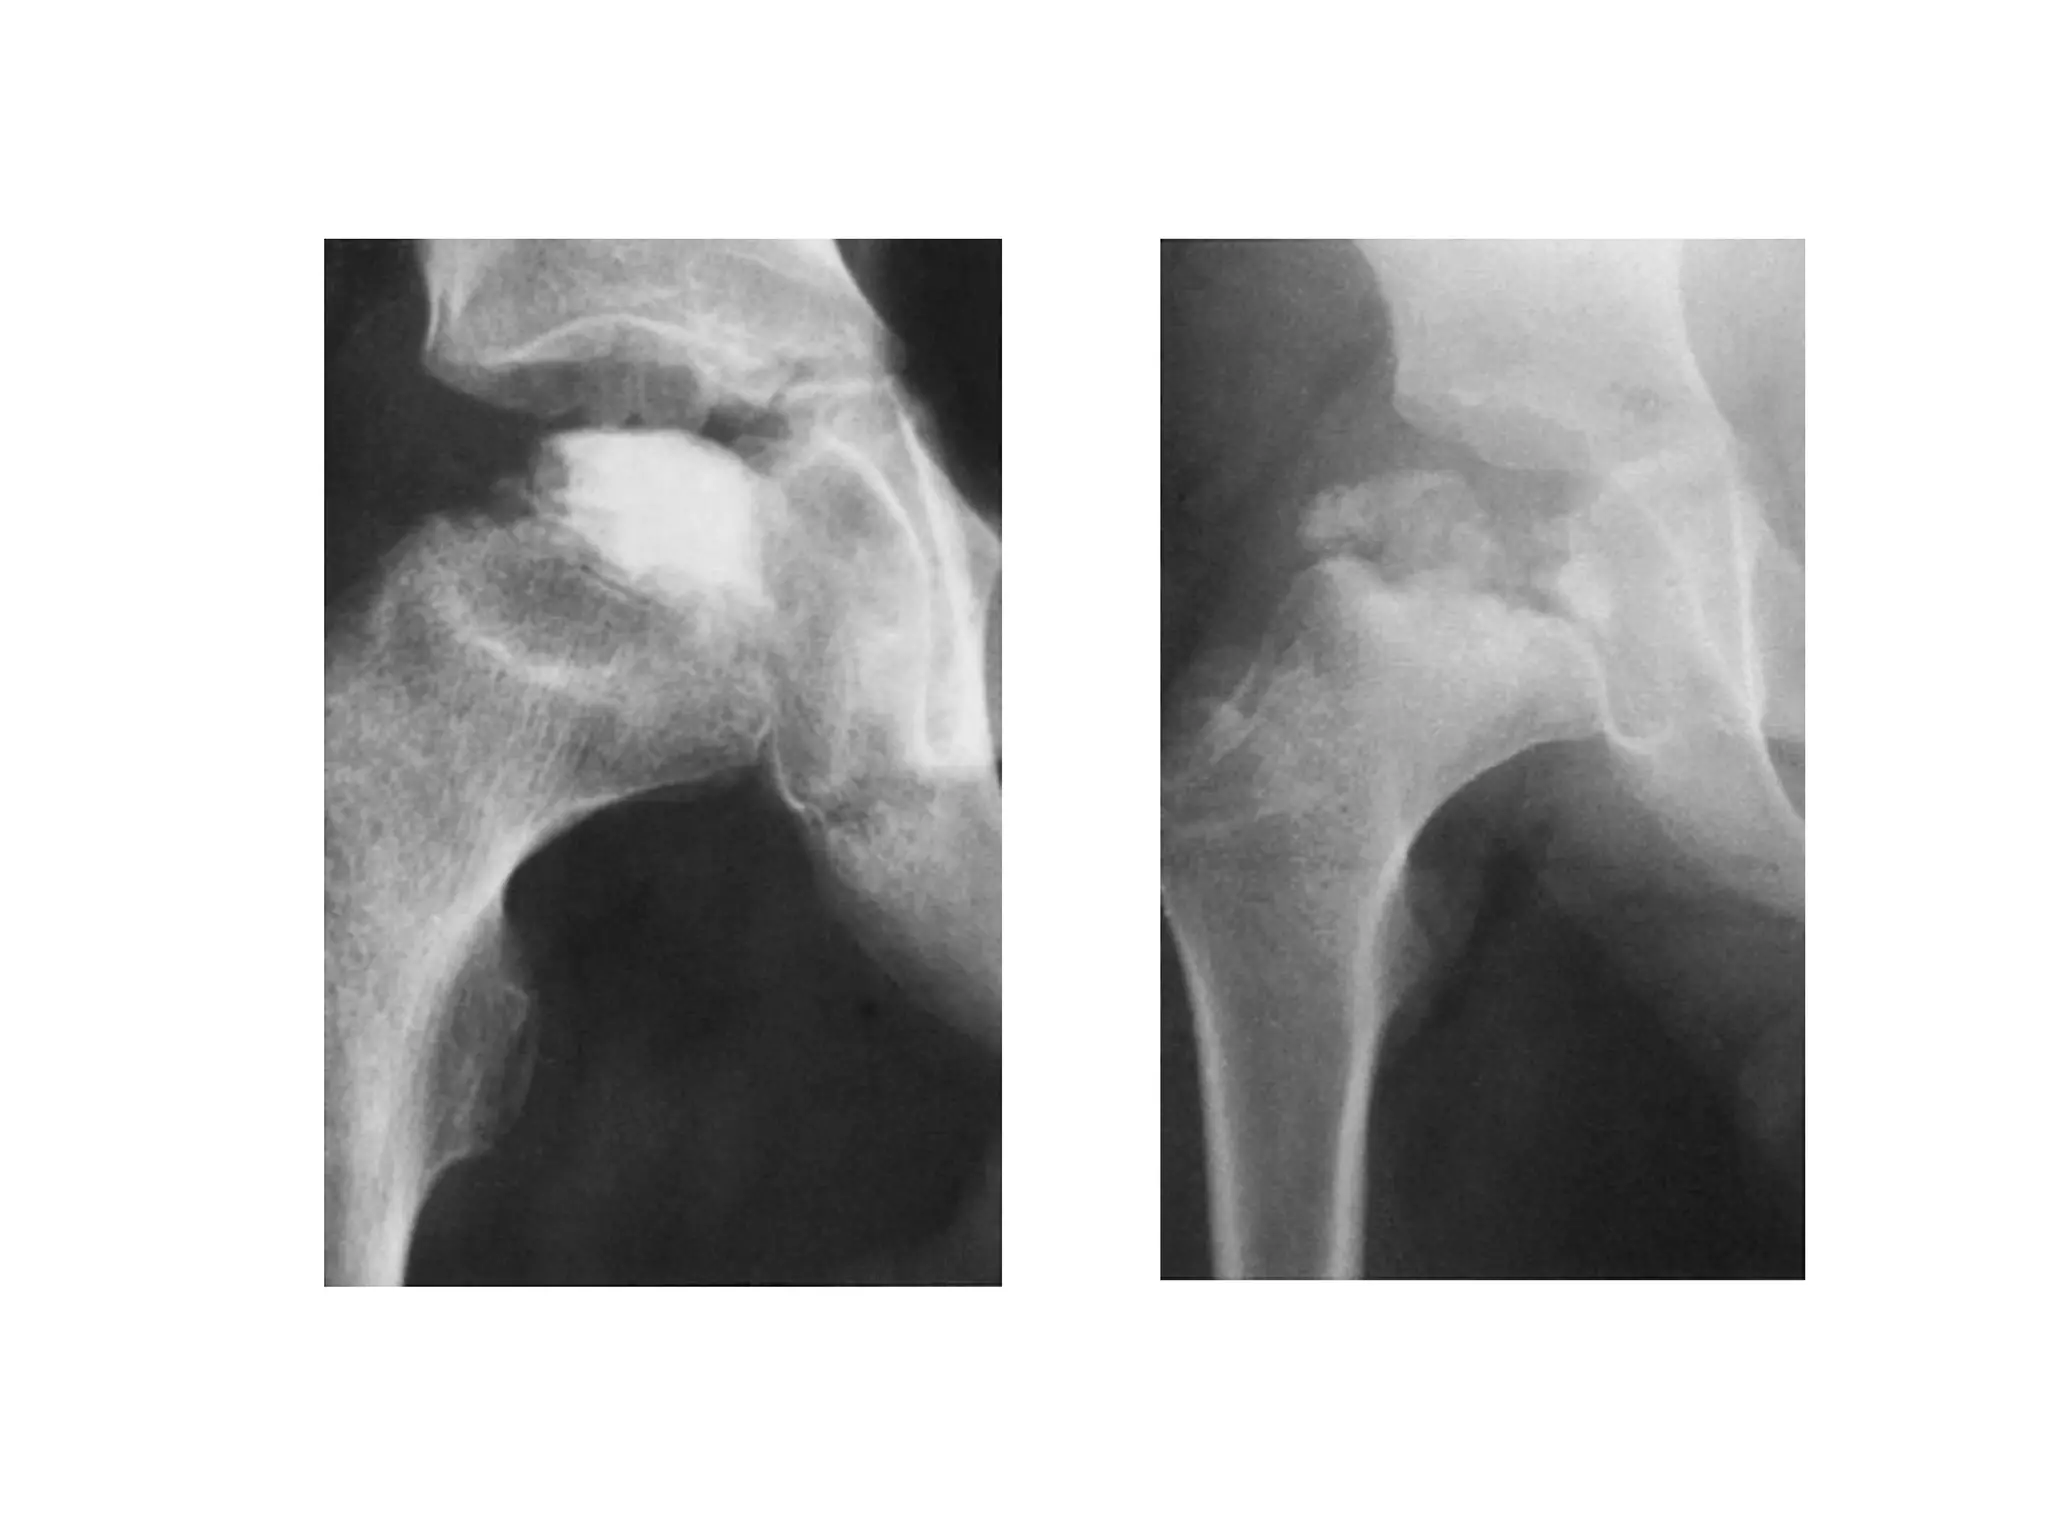

Perthes Disease

Head at Risk Sign

1. ‘V’ sign

2. Lateral Epiphyseal calcification

3. Lateral subluxation

4. Horizontal Epiphysis

5. Metaphyseal Changes

any 2 out of 5

Head at RiskSign 1. ‘V’ sign 2. Lateral Epiphyseal calcification 3. Lateral subluxation 4. Horizontal Epiphysis 5. Metaphyseal Changes any 2 out of 5